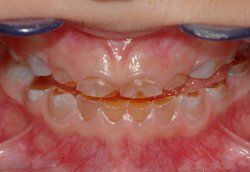

Milchgebiss eines 5-jährigen Kindes mit Dentinogenesis imperfecta. Die Zahnkronen sind bereits stark abgenutzt und typisch bernsteinfarben.

Betroffen sind immer alle Zähne sowohl im Milchgebiss als auch im bleibenden Gebiss. Typischerweise haben die Milchzähne eine bernsteinartige Farbe während die bleibenden Zähne eher gräulich erscheinen. Durch das mindermineralisierte Dentin kommt es bei Kaubelastung schnell zu großflächigen Abplatzungen des Zahnschmelzes. Das weiche Dentin unterliegt dann einer raschen Abrasion (Abnutzung) und die Zahnkrone wirkt schon nach kurzer Zeit stark abgeschliffen.